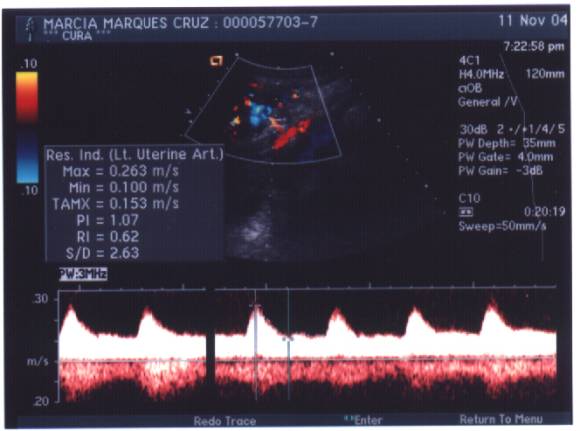

Mariah nasceu dia 29/dez/2004 às 08h40 com 1.880g e 41,5cm

:: Ultrasonografia 11/nov/2004 - IMG. 2 :: Ultrasonografia 11/nov/2004 - IMG. 2